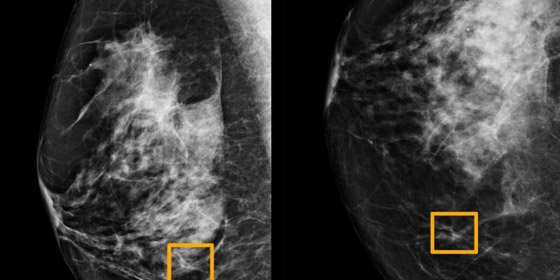

وقام الفريق، الذي شمل باحثين من إمبريال كوليدج لندن، والخدمة الصحية الوطنية في بريطانيا، بتدريب النظام لتحديد سرطان الثدي على عشرات الآلاف من فحوص الثدي بالأشعة السينية. ثم قارنوا توقعات النظام بالنتائج الفعلية لمجموعة تشمل 25856 تصويراً بالأشعة السينية للثدي في بريطانيا و3097 في الولايات المتحدة.

وأظهرت الدراسة أن نظام الذكاء الاصطناعي تمكن من تحديد الإصابة بالسرطان بدرجة مماثلة لدقة خبراء الأشعة، في حين خفض عدد النتائج الإيجابية الخاطئة بواقع 5.7 بالمئة في المجموعة الموجودة في الولايات المتحدة وبنسبة 2.1 بالمئة في تلك الكائنة في بريطانيا.

وخفض كذلك النتائج السلبية الخاطئة، التي صنفت الاختبارات خطأ على أنها طبيعية، 9.4 بالمئة في المجموعة الأميركية و2.7 بالمئة في المجموعة البريطانية. وتعكس هذه الاختلافات طرق قراءة نتائج تصوير الثدي بالأشعة السينية، ففي الولايات المتحدة، يقرأ خبير أشعة واحد فقط النتائج وتجرى الاختبارات كل عام أو عامين. أما في بريطانيا، فتجرى الاختبارات كل 3 سنوات ويطلع على كل منها خبيران للأشعة. وعندما يختلفان يُستشار خبير ثالث.